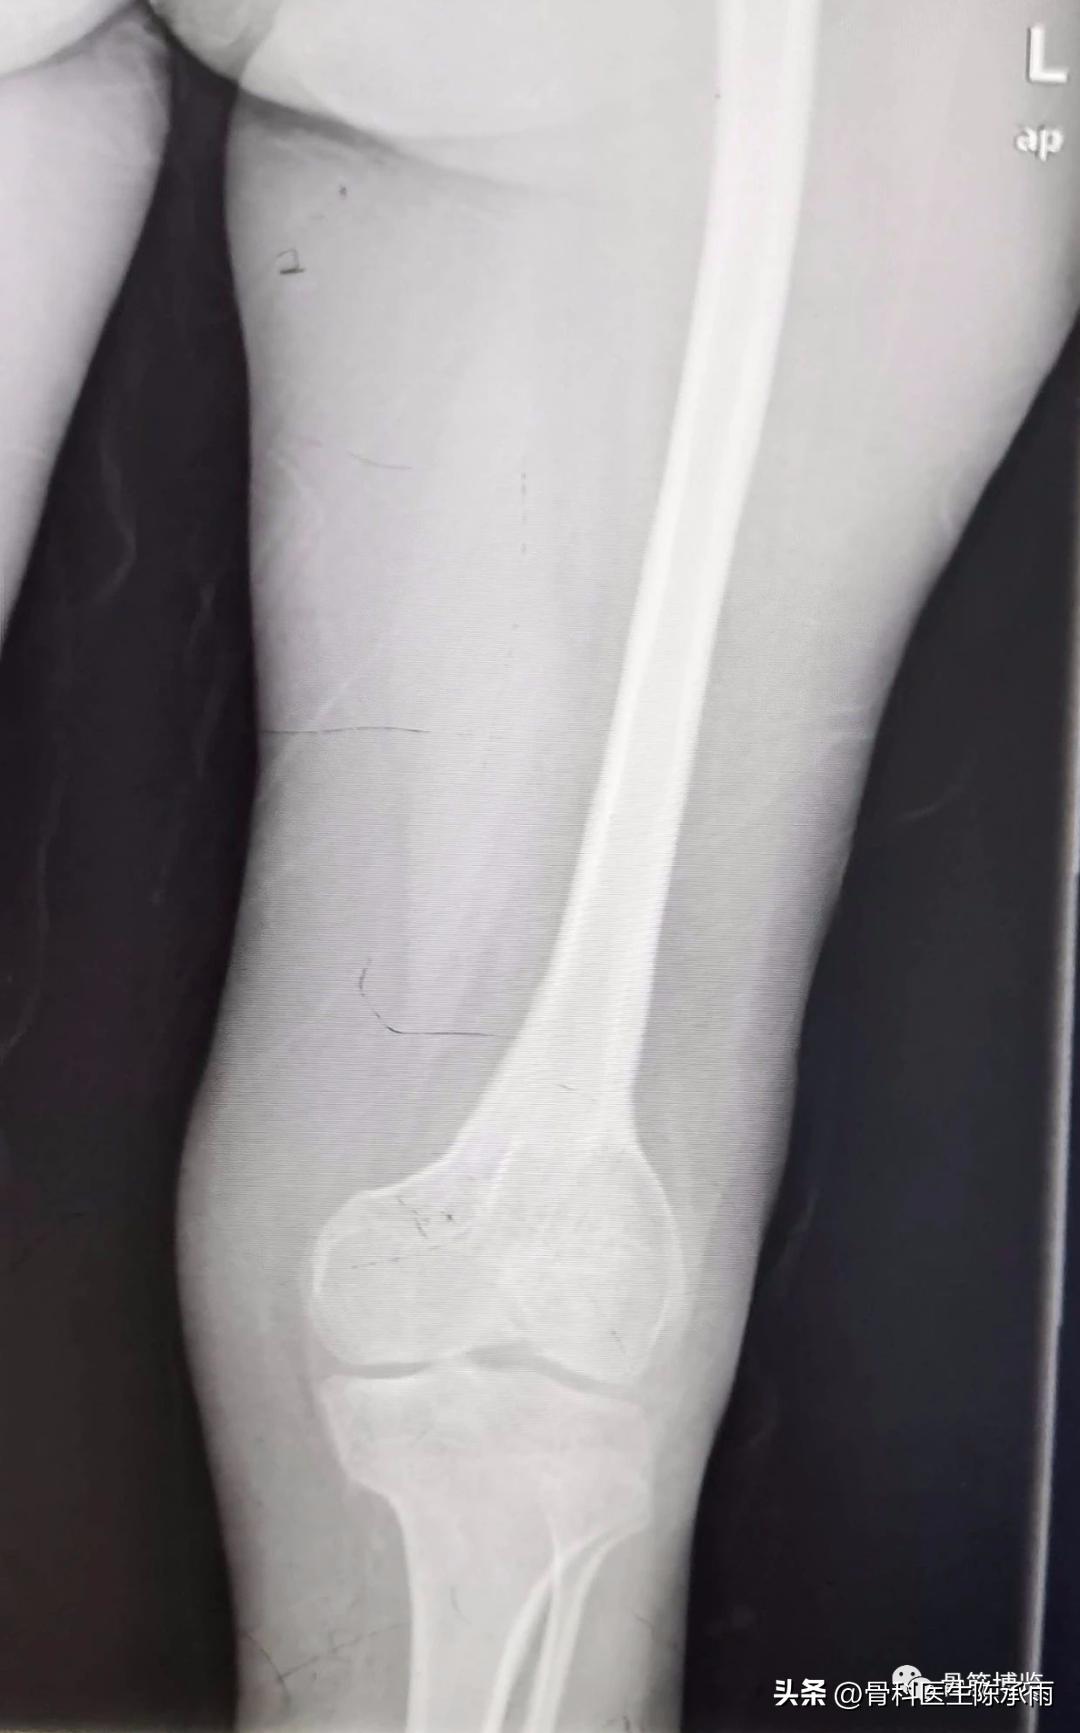

我们这例患者是一位脑瘫患者,患侧肢体短缩细小,股骨颈处及股骨髁上均做过截骨手术,失去了正常的角度,且股骨颈较细。给手术带来不小的难度。

术前尝试闭合复位,效果满意,决定行经皮穿钉,但股骨颈角度不正常,颈部细小,很难容得下3枚直径7.3空心钉,最后1枚空心钉部分切出股骨颈上缘。